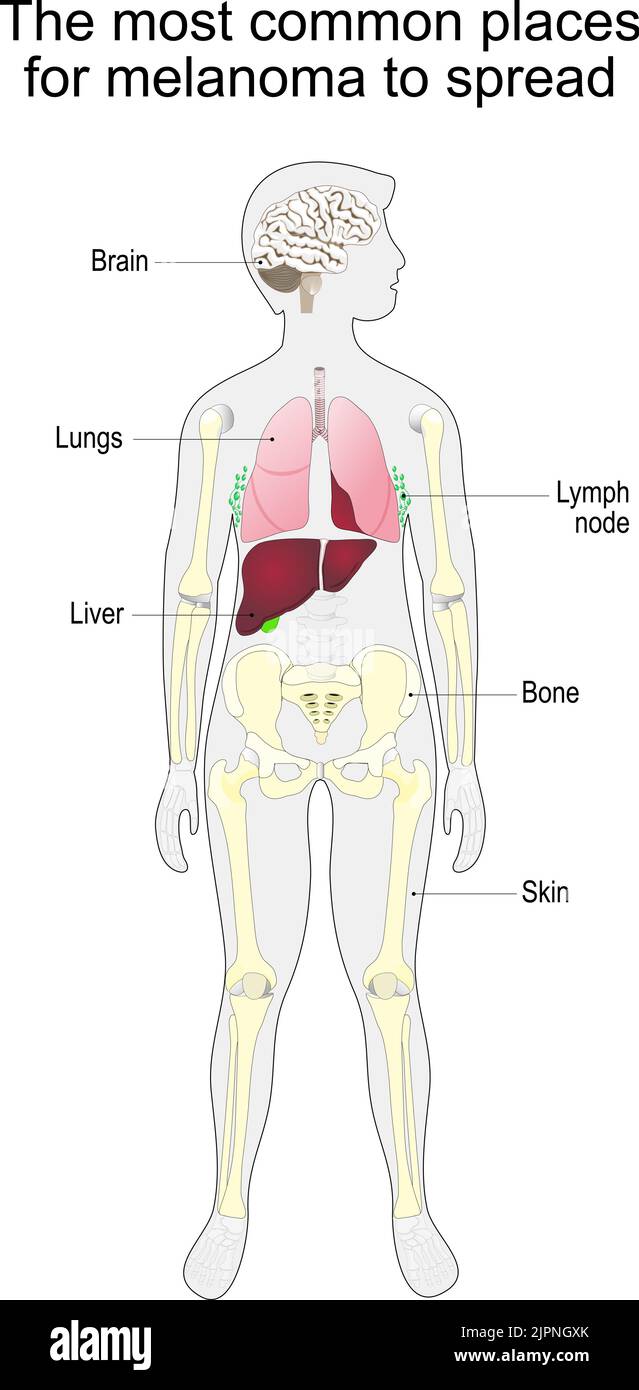

metastasis of skin cancer. malignant melanoma. The most common places for melanoma to spread. vector diagram Stock Vectorhttps://www.alamy.com/image-license-details/?v=1https://www.alamy.com/metastasis-of-skin-cancer-malignant-melanoma-the-most-common-places-for-melanoma-to-spread-vector-diagram-image478676651.html

metastasis of skin cancer. malignant melanoma. The most common places for melanoma to spread. vector diagram Stock Vectorhttps://www.alamy.com/image-license-details/?v=1https://www.alamy.com/metastasis-of-skin-cancer-malignant-melanoma-the-most-common-places-for-melanoma-to-spread-vector-diagram-image478676651.htmlRF2JPNGXK–metastasis of skin cancer. malignant melanoma. The most common places for melanoma to spread. vector diagram